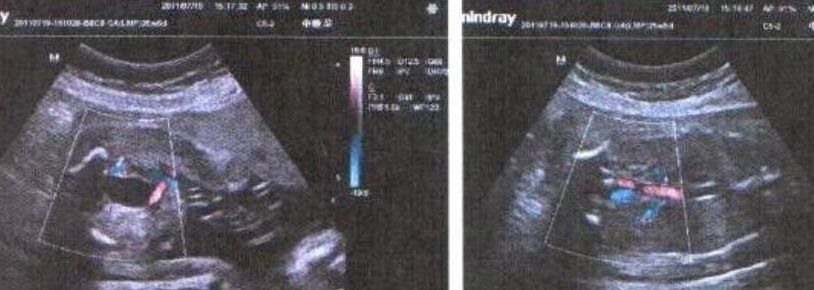

3,宝宝的双顶径

在怀孕之后,准妈妈在做B超的时候,不难发现,带检查单上会出现多种数据。他检查单上可能会根据宝宝的双顶径,以及宝宝的股骨长来判断宝宝是不适合顺产的条件。这时候我们的准妈妈也可以根据宝宝的双顶径来判断宝宝的性别,一般情况下,小王子的双顶径要比,小公主的双顶径要大一些。当然也可以,根据股骨长来进行推断。